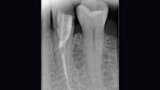

Fig. 1. Situación inicial: el diente 34 estaba fuertemente dañado. La encía se había adentrado en la cavidad.

Fig. 2. Estado tras la revisión, la colocación de la espiga y la reconstrucción.